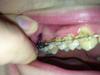

перетяжка зуба

мне перетягивают 7 на место 6

тянут на верхней челюсти резиновой цепочкой, но сейчас добавили пружину в распорку двух зубов , не особо понимаю для чего(((

long, пружина ставится именно как распорка, т.е. для увеличения расстояния между зубами, а стягивают зубы чейном - резиновой, очень прочной цепочкой.

У меня 8-ка перемещается на место удаленной 7-ки. Уже полтора года. НО.